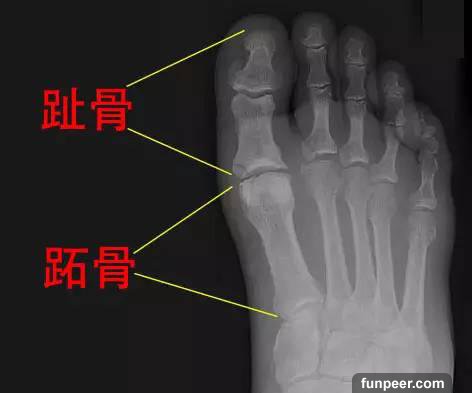

這是因為第一趾的跖骨特別短,導致走路和跑步時第一趾的受力被轉移到第二趾和第三趾,使這兩個腳趾根部容易長厚繭,即俗稱的「雞眼」,而且整個腳掌受力不均衡,還可造成轉移性前跖痛,以及下肢肌肉和關節的損傷,甚至引起背部和頸部的不適。嚴重者,如果症狀嚴重醫生會給患者設計相應的鞋墊、支具,甚至要做手術治療!!!北方有佳人 絕世而獨立